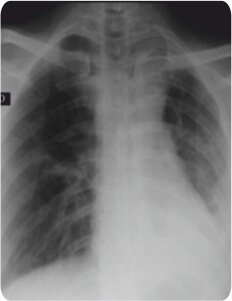

A 30 year old male with a history of Pulmonary Tuberculosis in 2010 & recurrence in 2018 came with a complaint of gradually progressive dyspnea over 2 years. He was presented with dyspnea even at rest and symptoms and signs of pleurisy.

Pre – Procedure